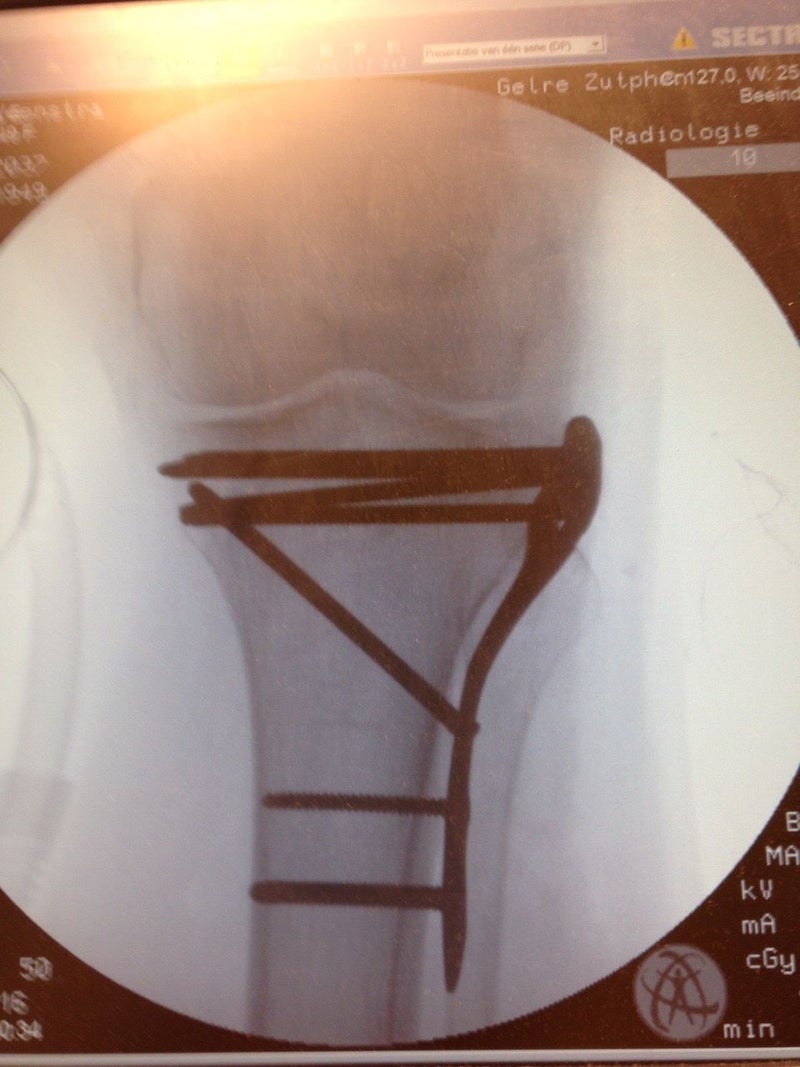

Het blijkt dat Everdien een tibia plateau fractuur heeft, een gebroken knie of eigenlijk is het plateau  van de knie , het dragende gedeelte van het scheenbeen, gebroken en verzakt. Daarom moet ze volgende week vrijdag geopereerd en worden er platen en schroeven ingezet.

De fysiotherapeut wilde kopieën hebben van de röntgen foto’s om te zien waar de plaat en de schroeven zitten zodat hij t.z.t. eventuele bewegingsbelemmeringen bij de therapie kan verklaren. Natuurlijk wilden wij ook de foto’s ook zien om goed te begrijpen wat de operatie behelsd heeft.

vooraanzicht knie, de schroeven door het bot zijn duidelijk te zien

Everdien begrijpt nu ook waarom ze op bepaalde plaatsen bot pijn heeft. Er zitten immers meerdere schroeven door het bot heen. Ze gebruikt nu 3 paracetamol per dag.